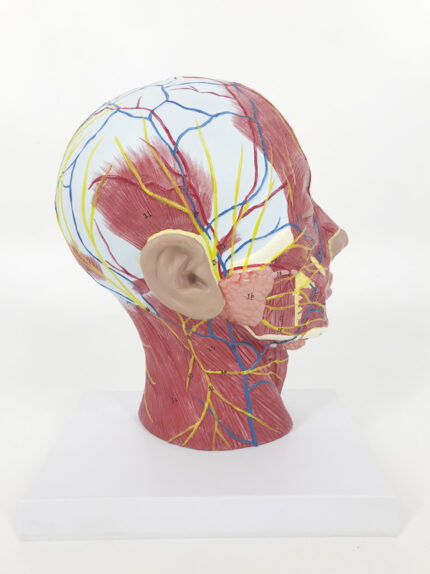

ATL-122 MUSCULAR MODEL OF HEAD AND NECK WITH VESSEL NERVES AND BRAIN 19 PARTS SOFT

ATL-131 HALF MUSCULAR HEAD WITH VESSEL SOFT

Life size model shows the right half of the human head and neck, sectioned along the sgittal plane. A superficial dissection exposes the facial muscles, the superficial blood vessels and nerve branches of the face and scalp, the parotid and submandibular glands. A median dissection expose the brain with its internal structure, tha pharynx and upper respiratiry tract, a section of the cervical vertebrae.